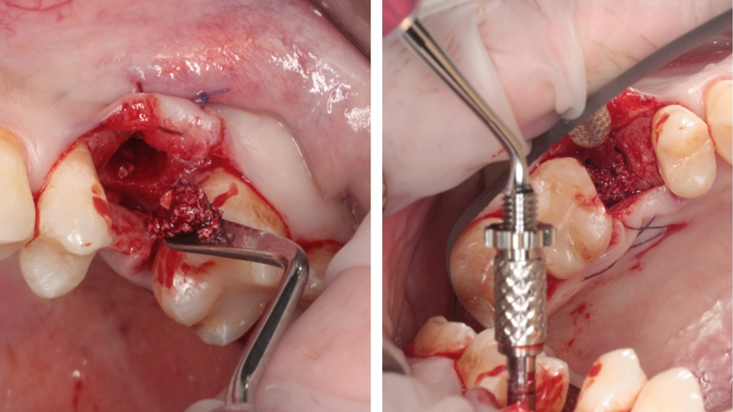

Clinical case: Ridge splitting technique using SmarThor + AnyRidge as expander

- Courtesy of Dr.Kwang-Bum Park, Korea -

Keywords

AnyRidge, ridge splitting, GBR, Dr. Kwang-Bum Park, mandibular posterior, SmartThor, Mega-Oss, thin ridge, bone regeneration

Products:

AnyRidge implant system. SmarThor, Mega-Oss